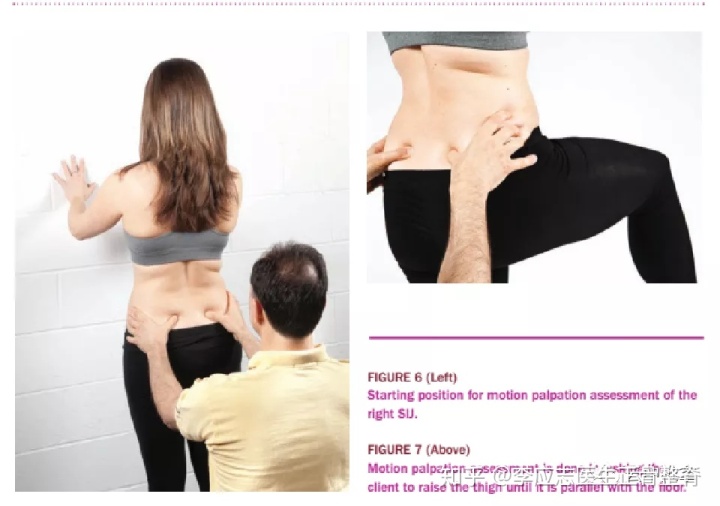

上图也是一种常见的骶髂关节错位的诊断方法,从动态活动中观察关节的对称性。